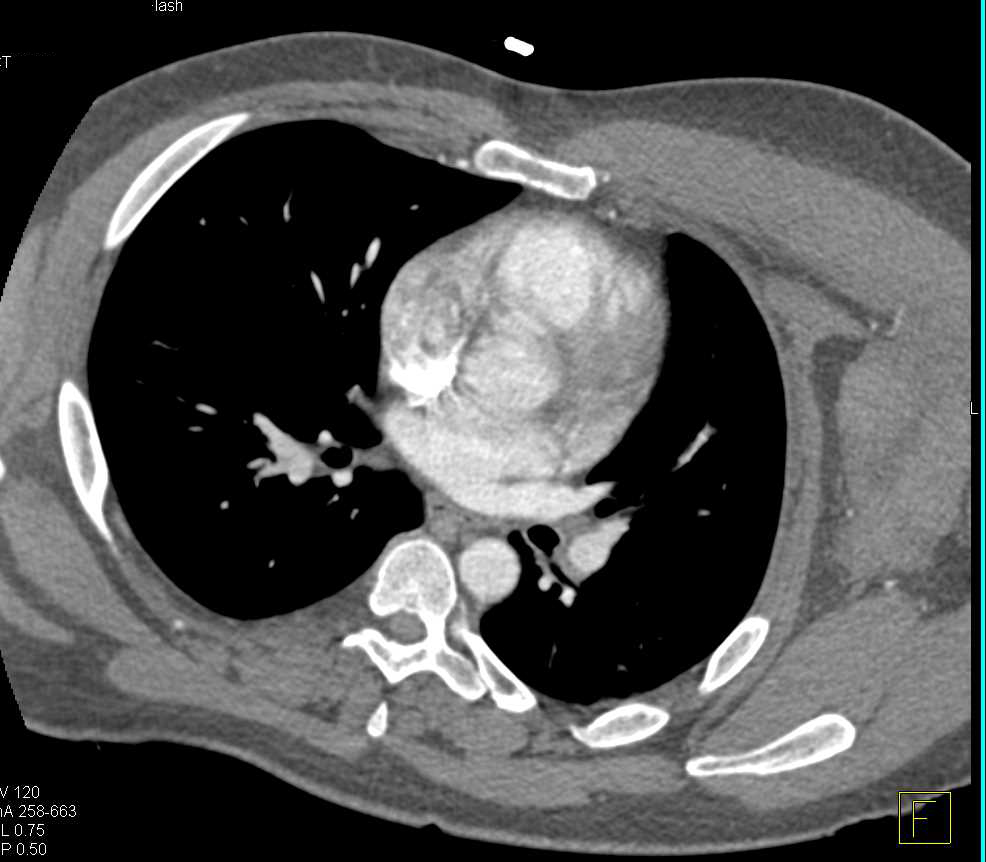

From www.researchgate.net

(a) Thorax CT scan evidencing left subpectoral hematoma; (b) computed Left Upper Chest Hematoma Icd 10 Nontraumatic hematoma of soft tissue. The 2025 edition of icd. Extrapleural hematomas are uncommon and usually seen in the context of rib fracture, subclavian venous catheter traumatic insertion,. Evacuation left upper extremity brachial sheath hematoma. * brachial sheath hematoma [t14.8xxa] procedure (s): Left Upper Chest Hematoma Icd 10.